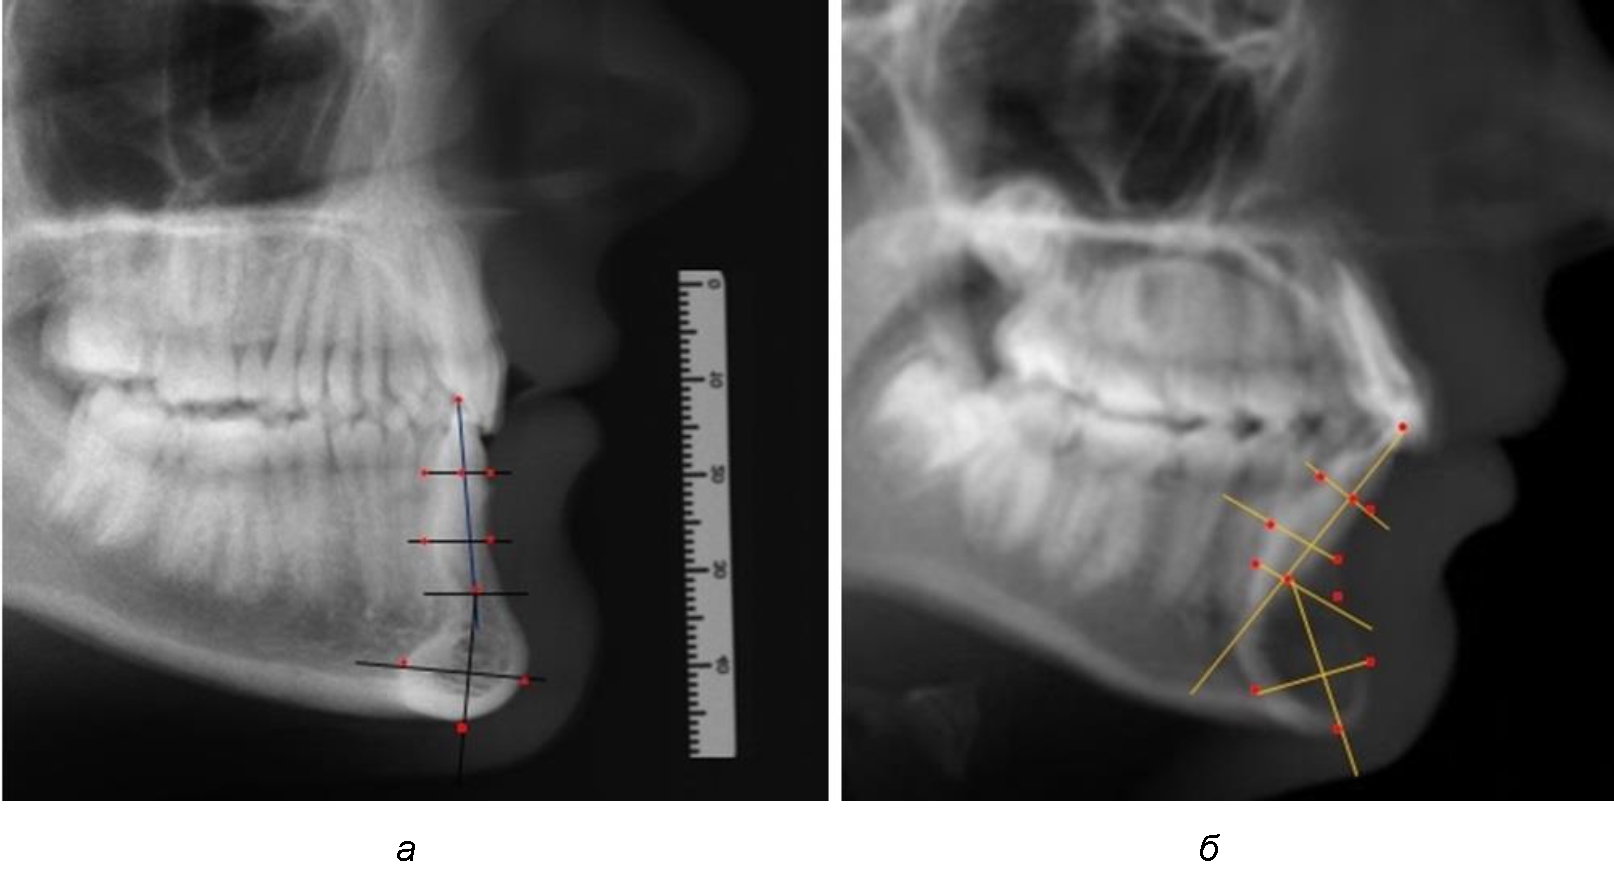

При анализе боковых телерентгенограмм использовали фрагменты гнатической части, на которых оценивали вертикальные и сагиттальные параметры резцового нижнечелюстного сегмента, на который наносили те же ориентиры, что и при анализе нативных препаратов и их рентгенограмм.

При необходимости и/или возможности проведения КЛКТ-исследования проводили анализ с сопоставлением фрагмента, что повышало точность диагностических мероприятий (рис. 2).

Рис. 2. Фрагменты ТРГ с ориентирами для измерения параметров резцового сегмента (а) и с наложением фрагмента КЛКТ (б)

Варианты резцовых сегментов нижней челюсти различные как по ширине, так и по высоте, а также по расхождению положения апикальных точек по Downs и Schwarz представлены на рис. 4.

Рис. 4. Особенности нижнечелюстного резцового сегмента на ТРГ у людей при среднем (а), широком (б) и узком (в) вариантах